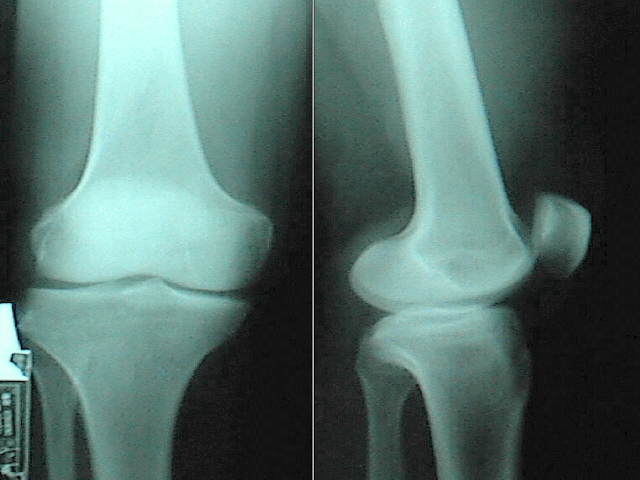

cat reaction omg shocked shock